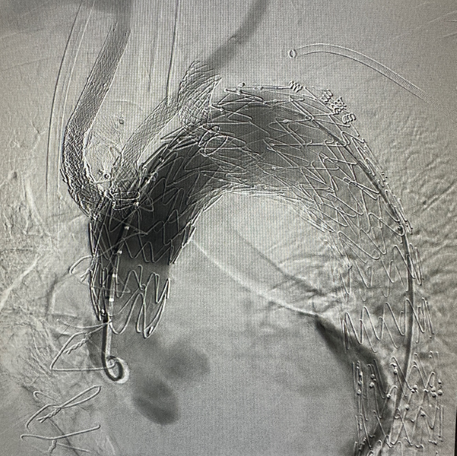

Hector™ Multi-Branch Thoracic Stent Graft System is intended to be used to treat aortic arch lesions requiring reconstruction of the three supra-aortic branches with ≥20mm healthy landing zone proximal to the lesions, as prescribed by the physician. The device restores aortic flow through the stent graft intimal lumen and maintaining aortic arch triple-branch perfusion.